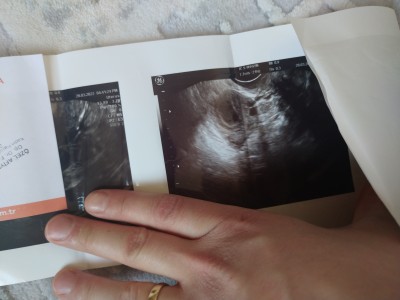

Arkadaslar bir şey gözüküyor mu doktor dört haftalık dedi ben bir şey goremedim anlayan var mı?

Sadece kese var yuvarlak küçük

Kese var sadece cnm. Bi kac haftaya bebek gozle gorunur hale gelir. Ben 6 haftalikken gittim. Kenara yapismis nokta gibiydi:) zar zor gorunuyodu. Rabbim hayirli evlat nasip etsin gozun aydin insallah

Maşallah 4 haftada kese görünmüş♥️ benim 5.haftada görünmüştü. Allah bağışlasın sağlıkla kucağınıza alın kafanıza hiçbir şeyi takmayın ben o kadar stresler yaşadım ki ya bi aksilik olursa diye şimdi geriye bakıp halime gülüyorum:))güzelce dinlenin bebişinizin hayalini kurun en tatlı zamanlarımız bunlar♥️♥️♥️